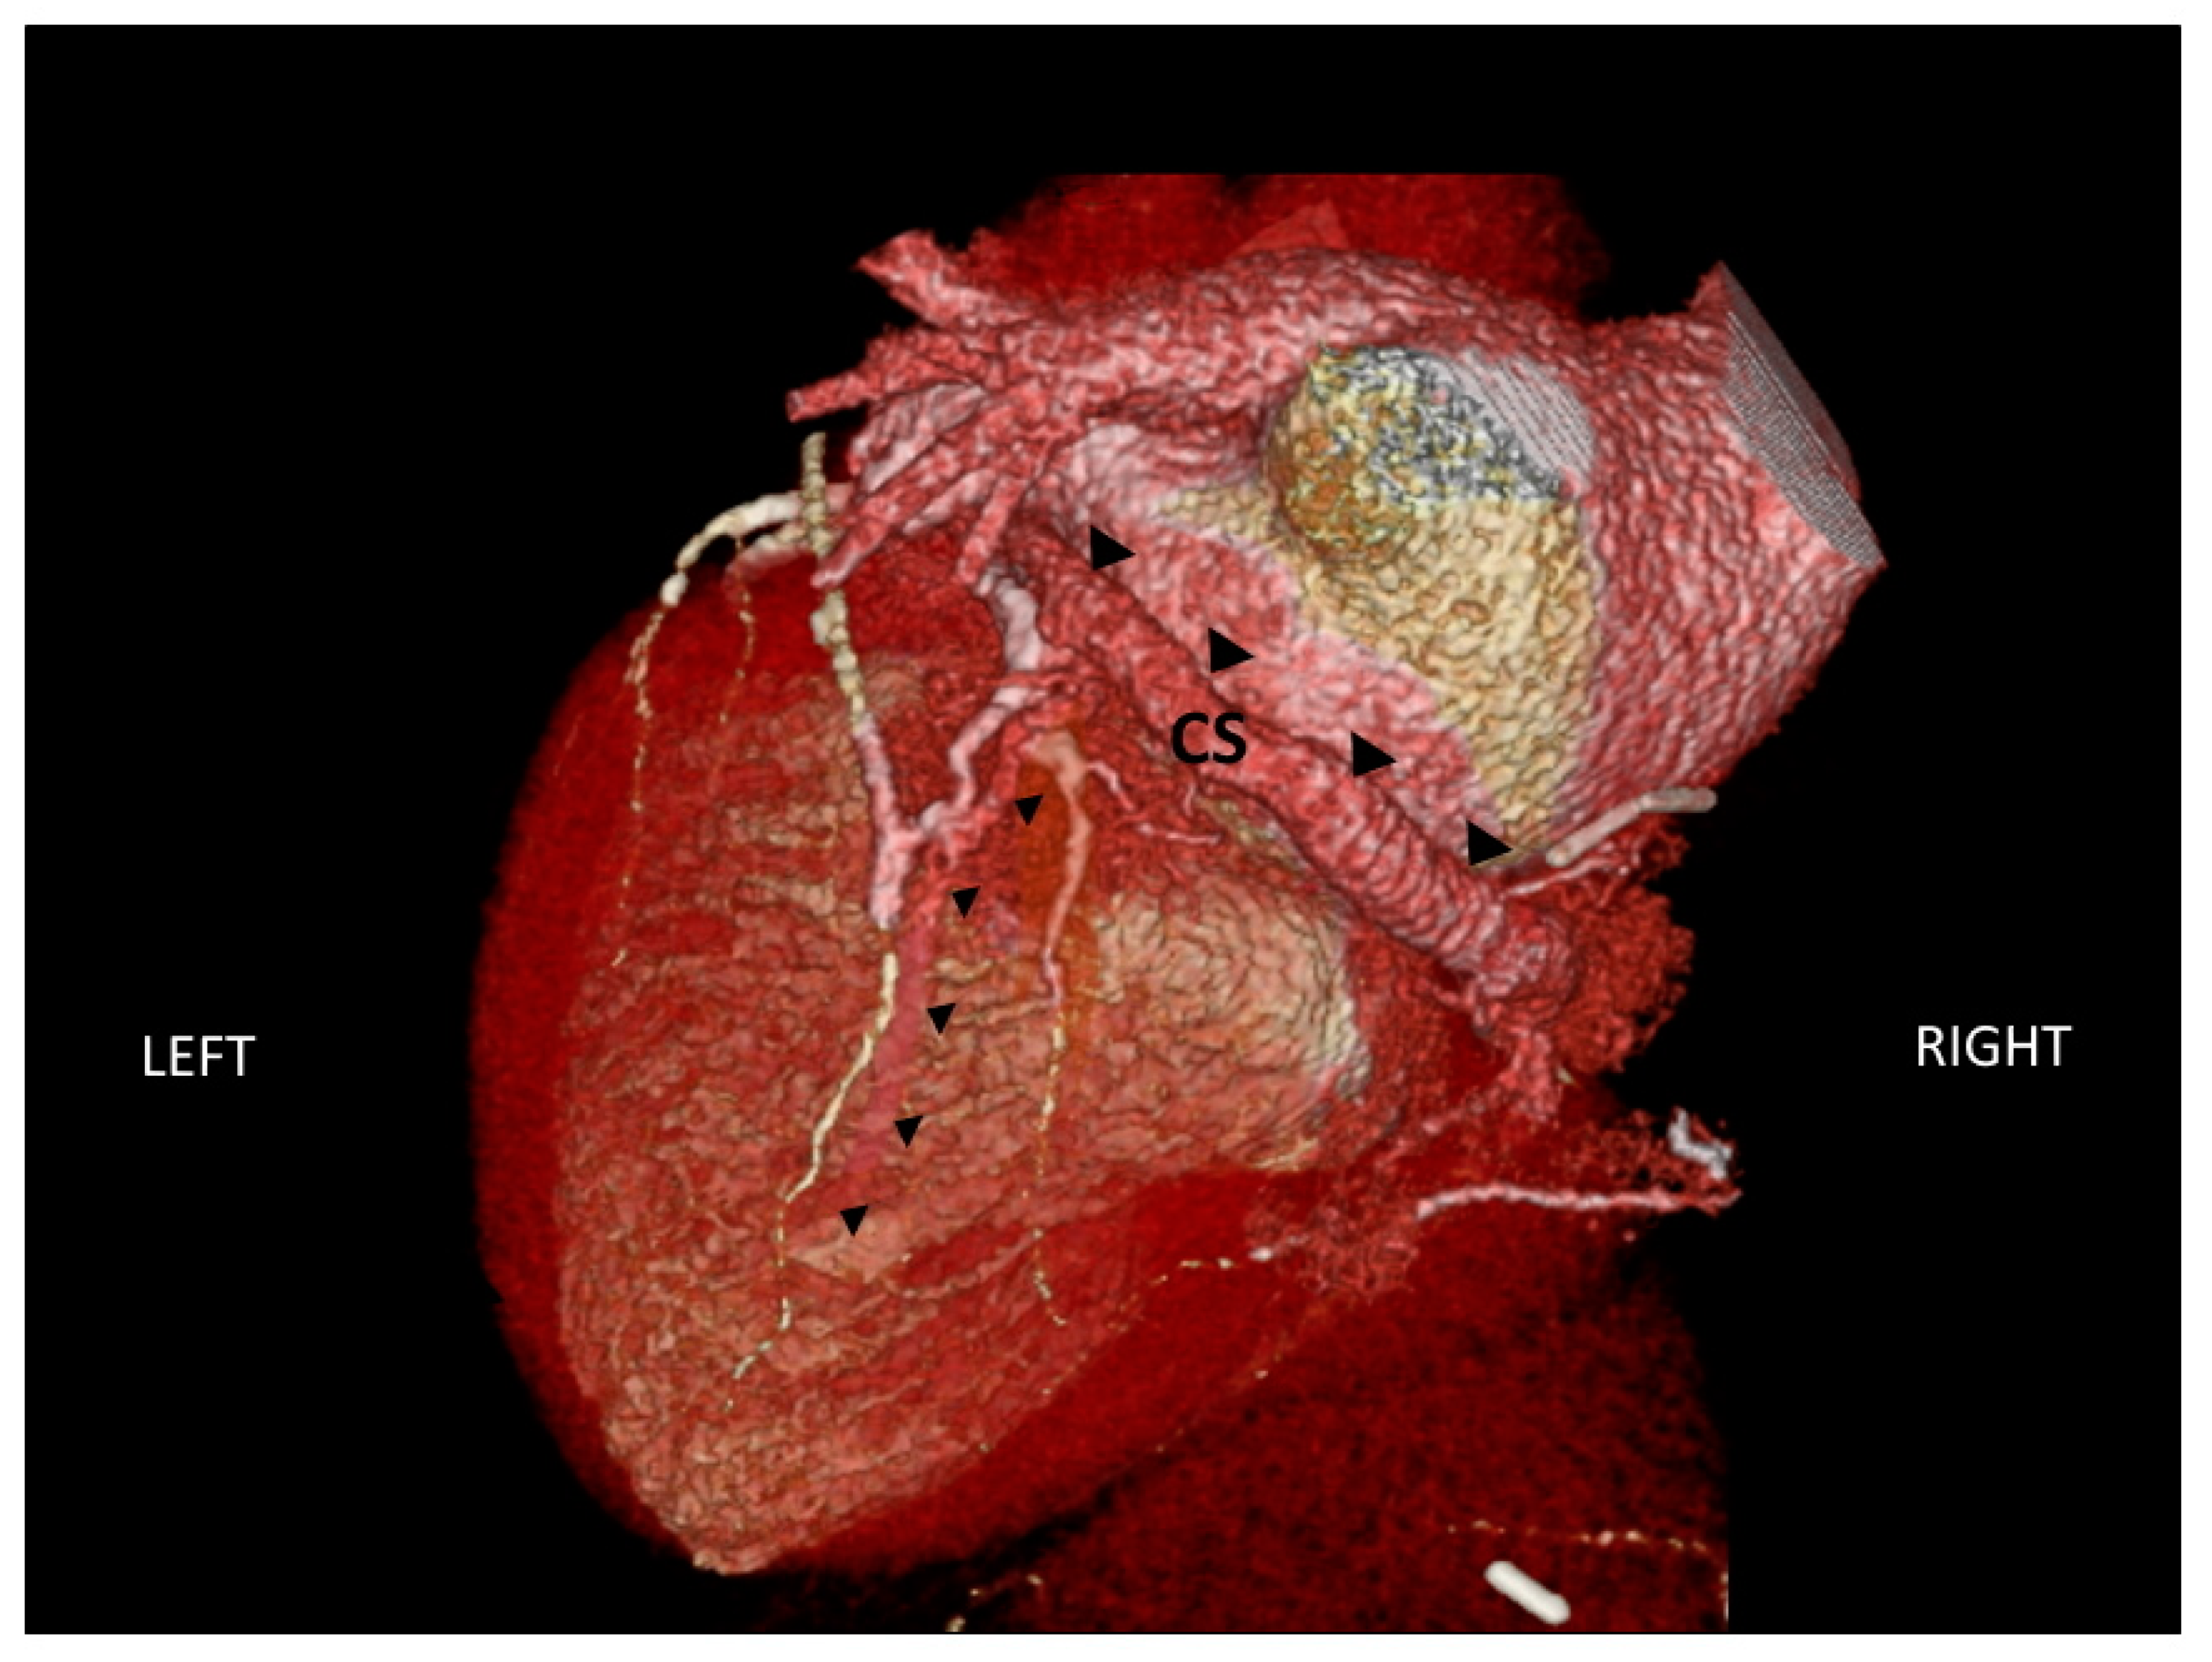

2.3. Assessment of Cardiac Venous Anatomy

- Van de Veire, N.R.; Schuijf, J.D.; De Sutter, J.; Devos, D.; Bleeker, G.B.; de Roos, A.; van der Wall, E.E.; Schalij, M.J.; Bax, J.J. Non-invasive visualization of the cardiac venous system in coronary artery disease patients using 64-slice computed tomography. J. Am. Coll. Cardiol. 2006, 48, 1832–1838. [Google Scholar] [CrossRef] [PubMed]

- Girsky, M.J.; Shinbane, J.S.; Ahmadi, N.; Mao, S.; Flores, F.; Budoff, M.J. Prospective randomized trial of venous cardiac computed tomographic angiography for facilitation of cardiac resynchronization therapy. Pacing Clin. Electrophysiol. 2010, 33, 1182–1187. [Google Scholar] [CrossRef] [PubMed]

- Tada, T.; Osuda, K.; Nakata, T.; Muranaka, I.; Himeno, M.; Muratsubaki, S.; Murase, H.; Sato, K.; Hirose, M.; Fukuma, T. A novel approach to the selection of an appropriate pacing position for optimal cardiac resynchronization therapy using CT coronary venography and myocardial perfusion imaging: FIVE STaR method (fusion image using CT coronary venography and perfusion SPECT applied for cardiac resynchronization therapy). J. Nucl. Cardiol. 2019, in press. [Google Scholar]

- Salden, O.A.E.; van den Broek, H.T.; van Everdingen, W.M.; Mohamed Hoesein, F.A.A.; Velthuis, B.K.; Doevendans, P.A.; Cramer, M.J.; Tuinenburg, A.E.; Leufkens, P.; van Slochteren, F.J.; et al. Multimodality imaging for real-time image-guided left ventricular lead placement during cardiac resynchronization therapy implantations. Int. J. Cardiovasc. Imaging 2019, 35, 1327–1337. [Google Scholar] [CrossRef] [Green Version]